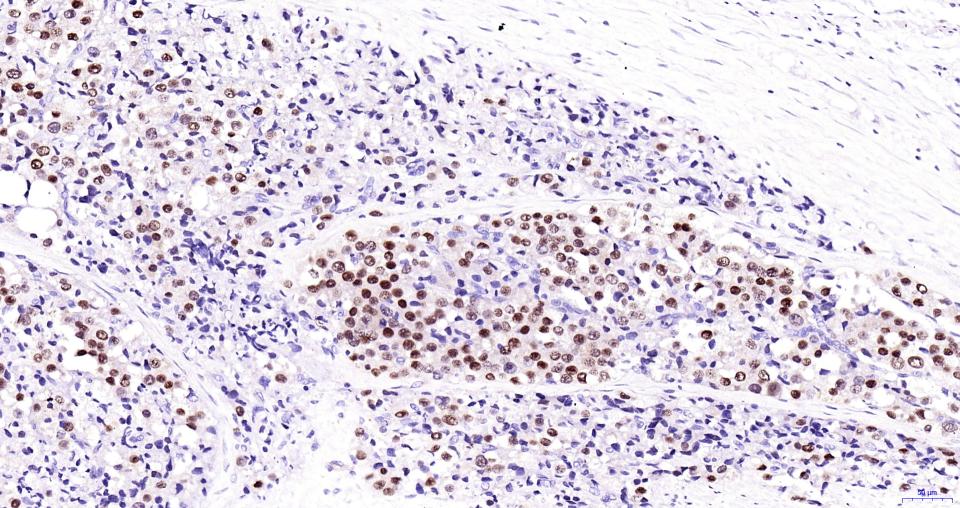

| 英文名称 | AR/Androgen Receptor Rabbit pAb |

| 中文名称 | 雄激素受体(AR)抗体 |

| 产品应用 | WB=1:500-2000, IHC-P=1:50-200, IHC-F=1:50-200, IF=1:50-200 Not yet tested in other applications. |

| {IHC-P} | {1:50-200} |